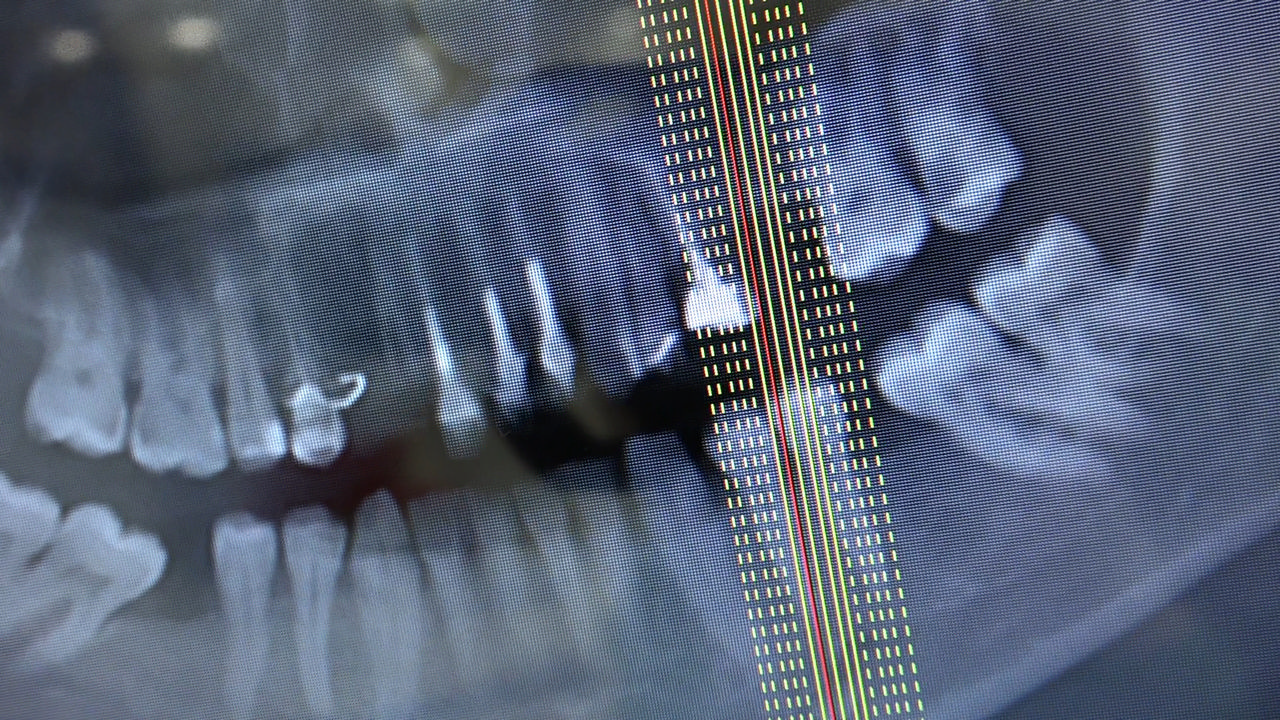

7 Sesja X Sezonu Practiculum Implantologii, w której brali udział kursanci z Grupy A i B, obejmowała implantacje wykonane systemem Axiom, procedury regeneracyjne tkanki kostnej i zabieg sinus lift oraz procedury implantoptotetyczne. Ten zakres szkolenia poprowadziła dr Małgorzata Piotrowska. Protetyka na implantach, to finalny etap leczenia implantologicznego decydujący o uzyskaniu harmonijnego łuku zębowego, okluzji oraz szczelności połączeń, a więc zadowoleniu Pacjenta i powodzeniu całego procesu leczenia.

Jego sednem jest wybór optymalnego rozwiązania rekonstrukcji protetycznej uwzględniający bardzo wiele czynników o charakterze mechanicznym, funkcjonalnym i estetycznym, związanych ze stanem tkanki kostnej, jamy ustnej i uzębienia. Odbywa się już na etapie tomografii komputerowej i jest ściśle powiązany z częścią chirurgiczną, ponieważ prawidłowe zaplanowanie pracy i usytuowania implantów wspomagane plastyką tkanek miękkich, to dla procedur protetycznych baza wyjściowa. Zasady te są jak najbardziej oczywiste, zarówno przy samodzielnym wykonywaniu leczenia implantologicznego, jak i przy podziale zadań dla chirurga i protetyka, czyli pracy w duecie.